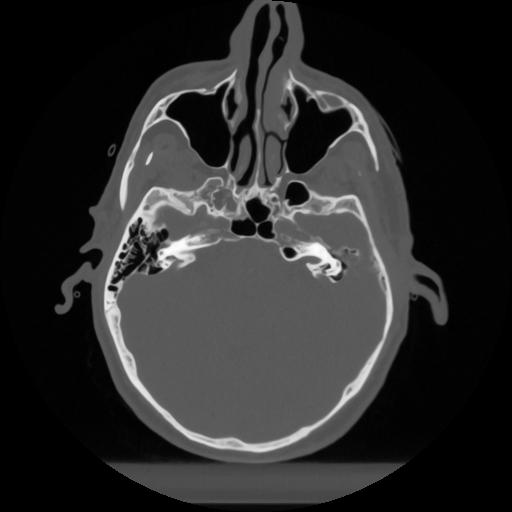

12 P.BLANDAS,,Vol,0.5,P.BLANDAS,,